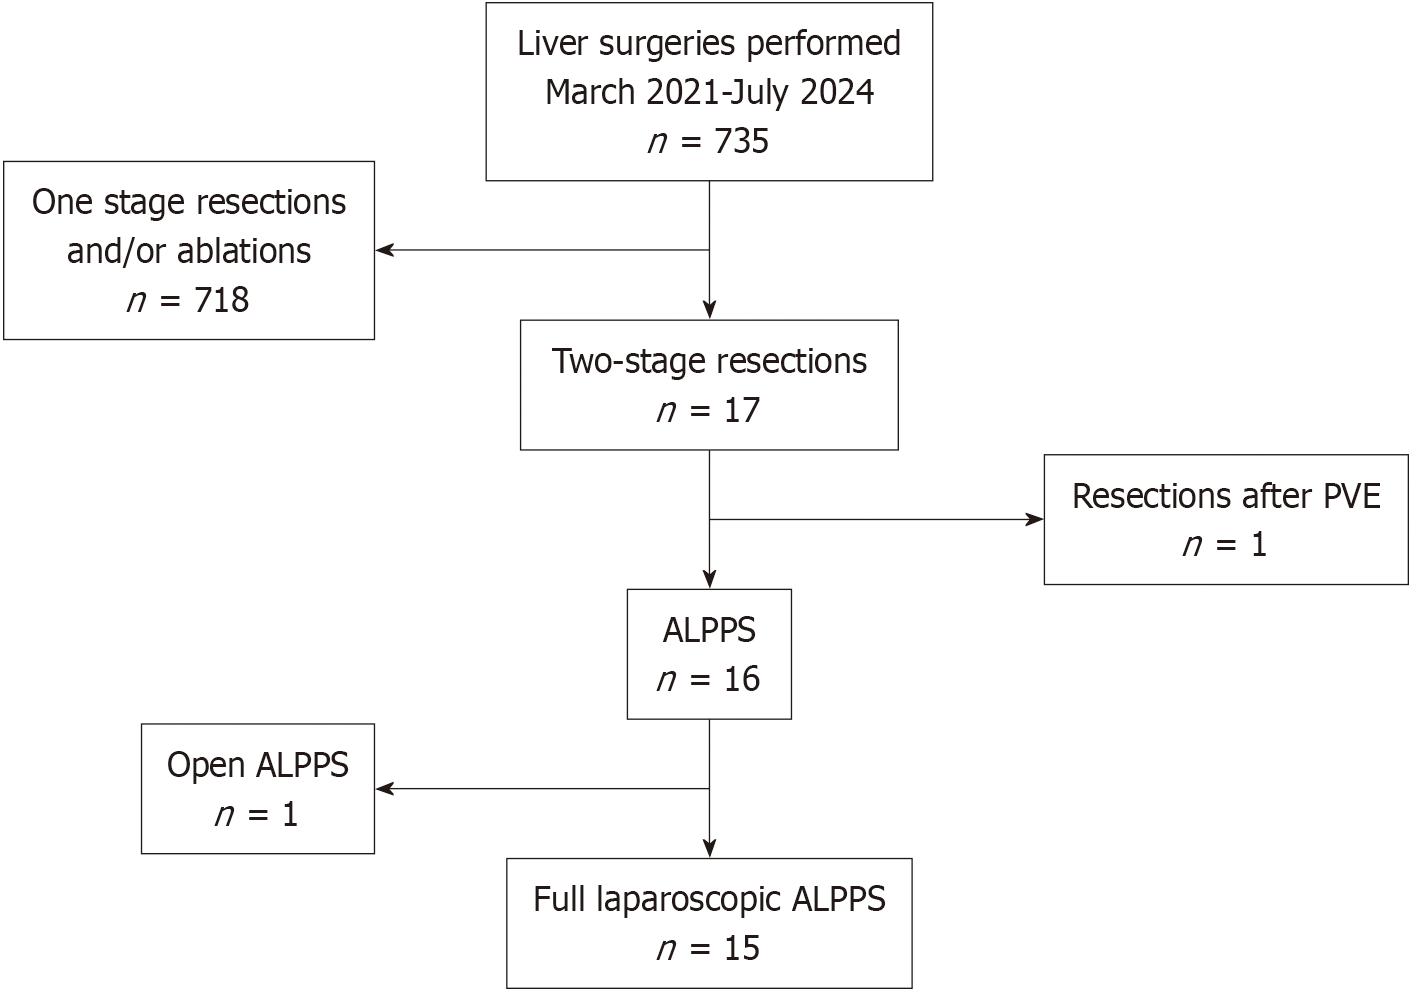

Figure 1 The flowchart shows all consecutive patients with colorectal liver metastases who underwent liver surgery at our institution between March 2021 and July 2024.

PVE: Portal venous embolization; ALPPS: Associating liver partition and portal vein ligation for staged hepatectomy.